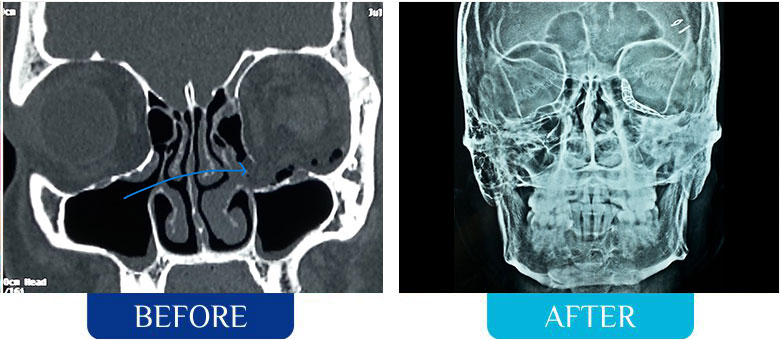

Facial Trauma / Fractures